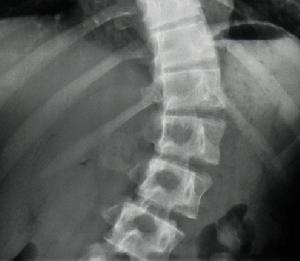

對於椎體鏇轉發生的評價,通常用Nash-Moe分型,即通過雙側椎弓根出現的對稱性多少來判斷。通過椎體椎弓根雙側的對稱性描述,從而在普通X線上得到椎體鏇轉的信息;(圖1-3)